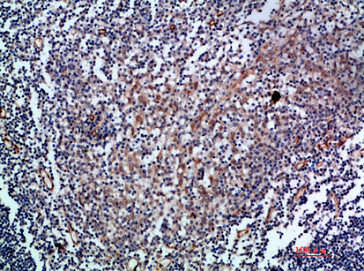

Immunohistochemical analysis of paraffin-embedded human-tonsil, antibody was diluted at 1:200